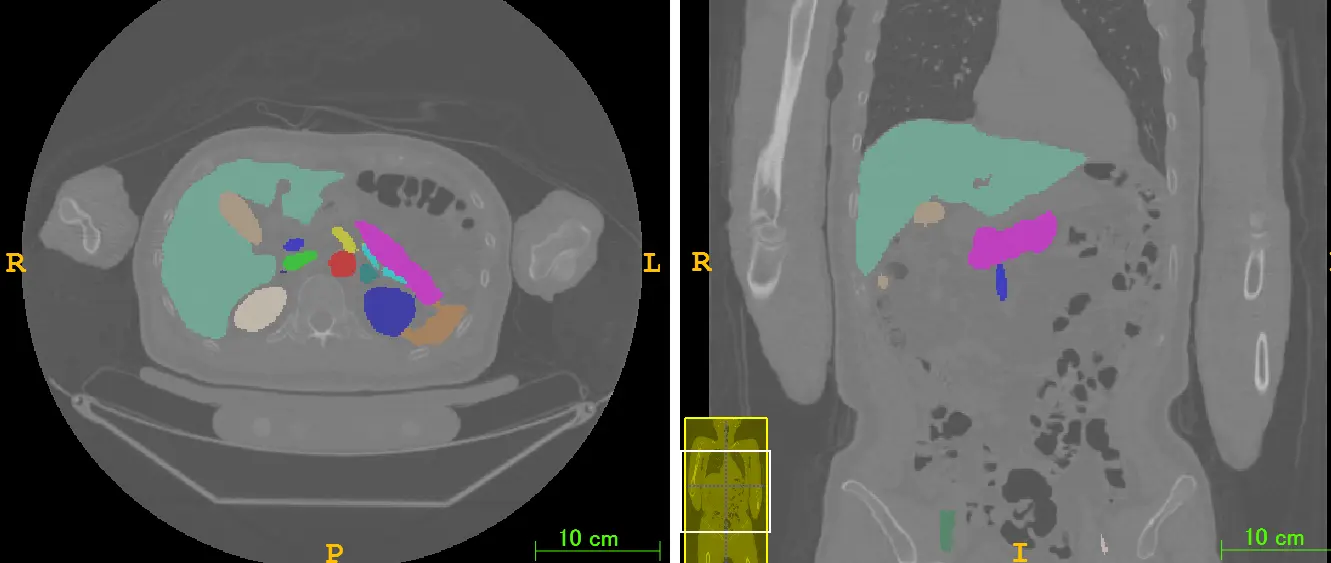

種々の疾患の自動検出

肝腫瘍・肺結節・気管支粘液栓など

内臓脂肪自動計測

成人病リスクを数値化

サルコペニアプロジェクト

内臓脂肪・皮下脂肪領域の抽出と筋肉量計測

解剖学的ランドマーク検出

人体の特徴的構造を頑強に検出